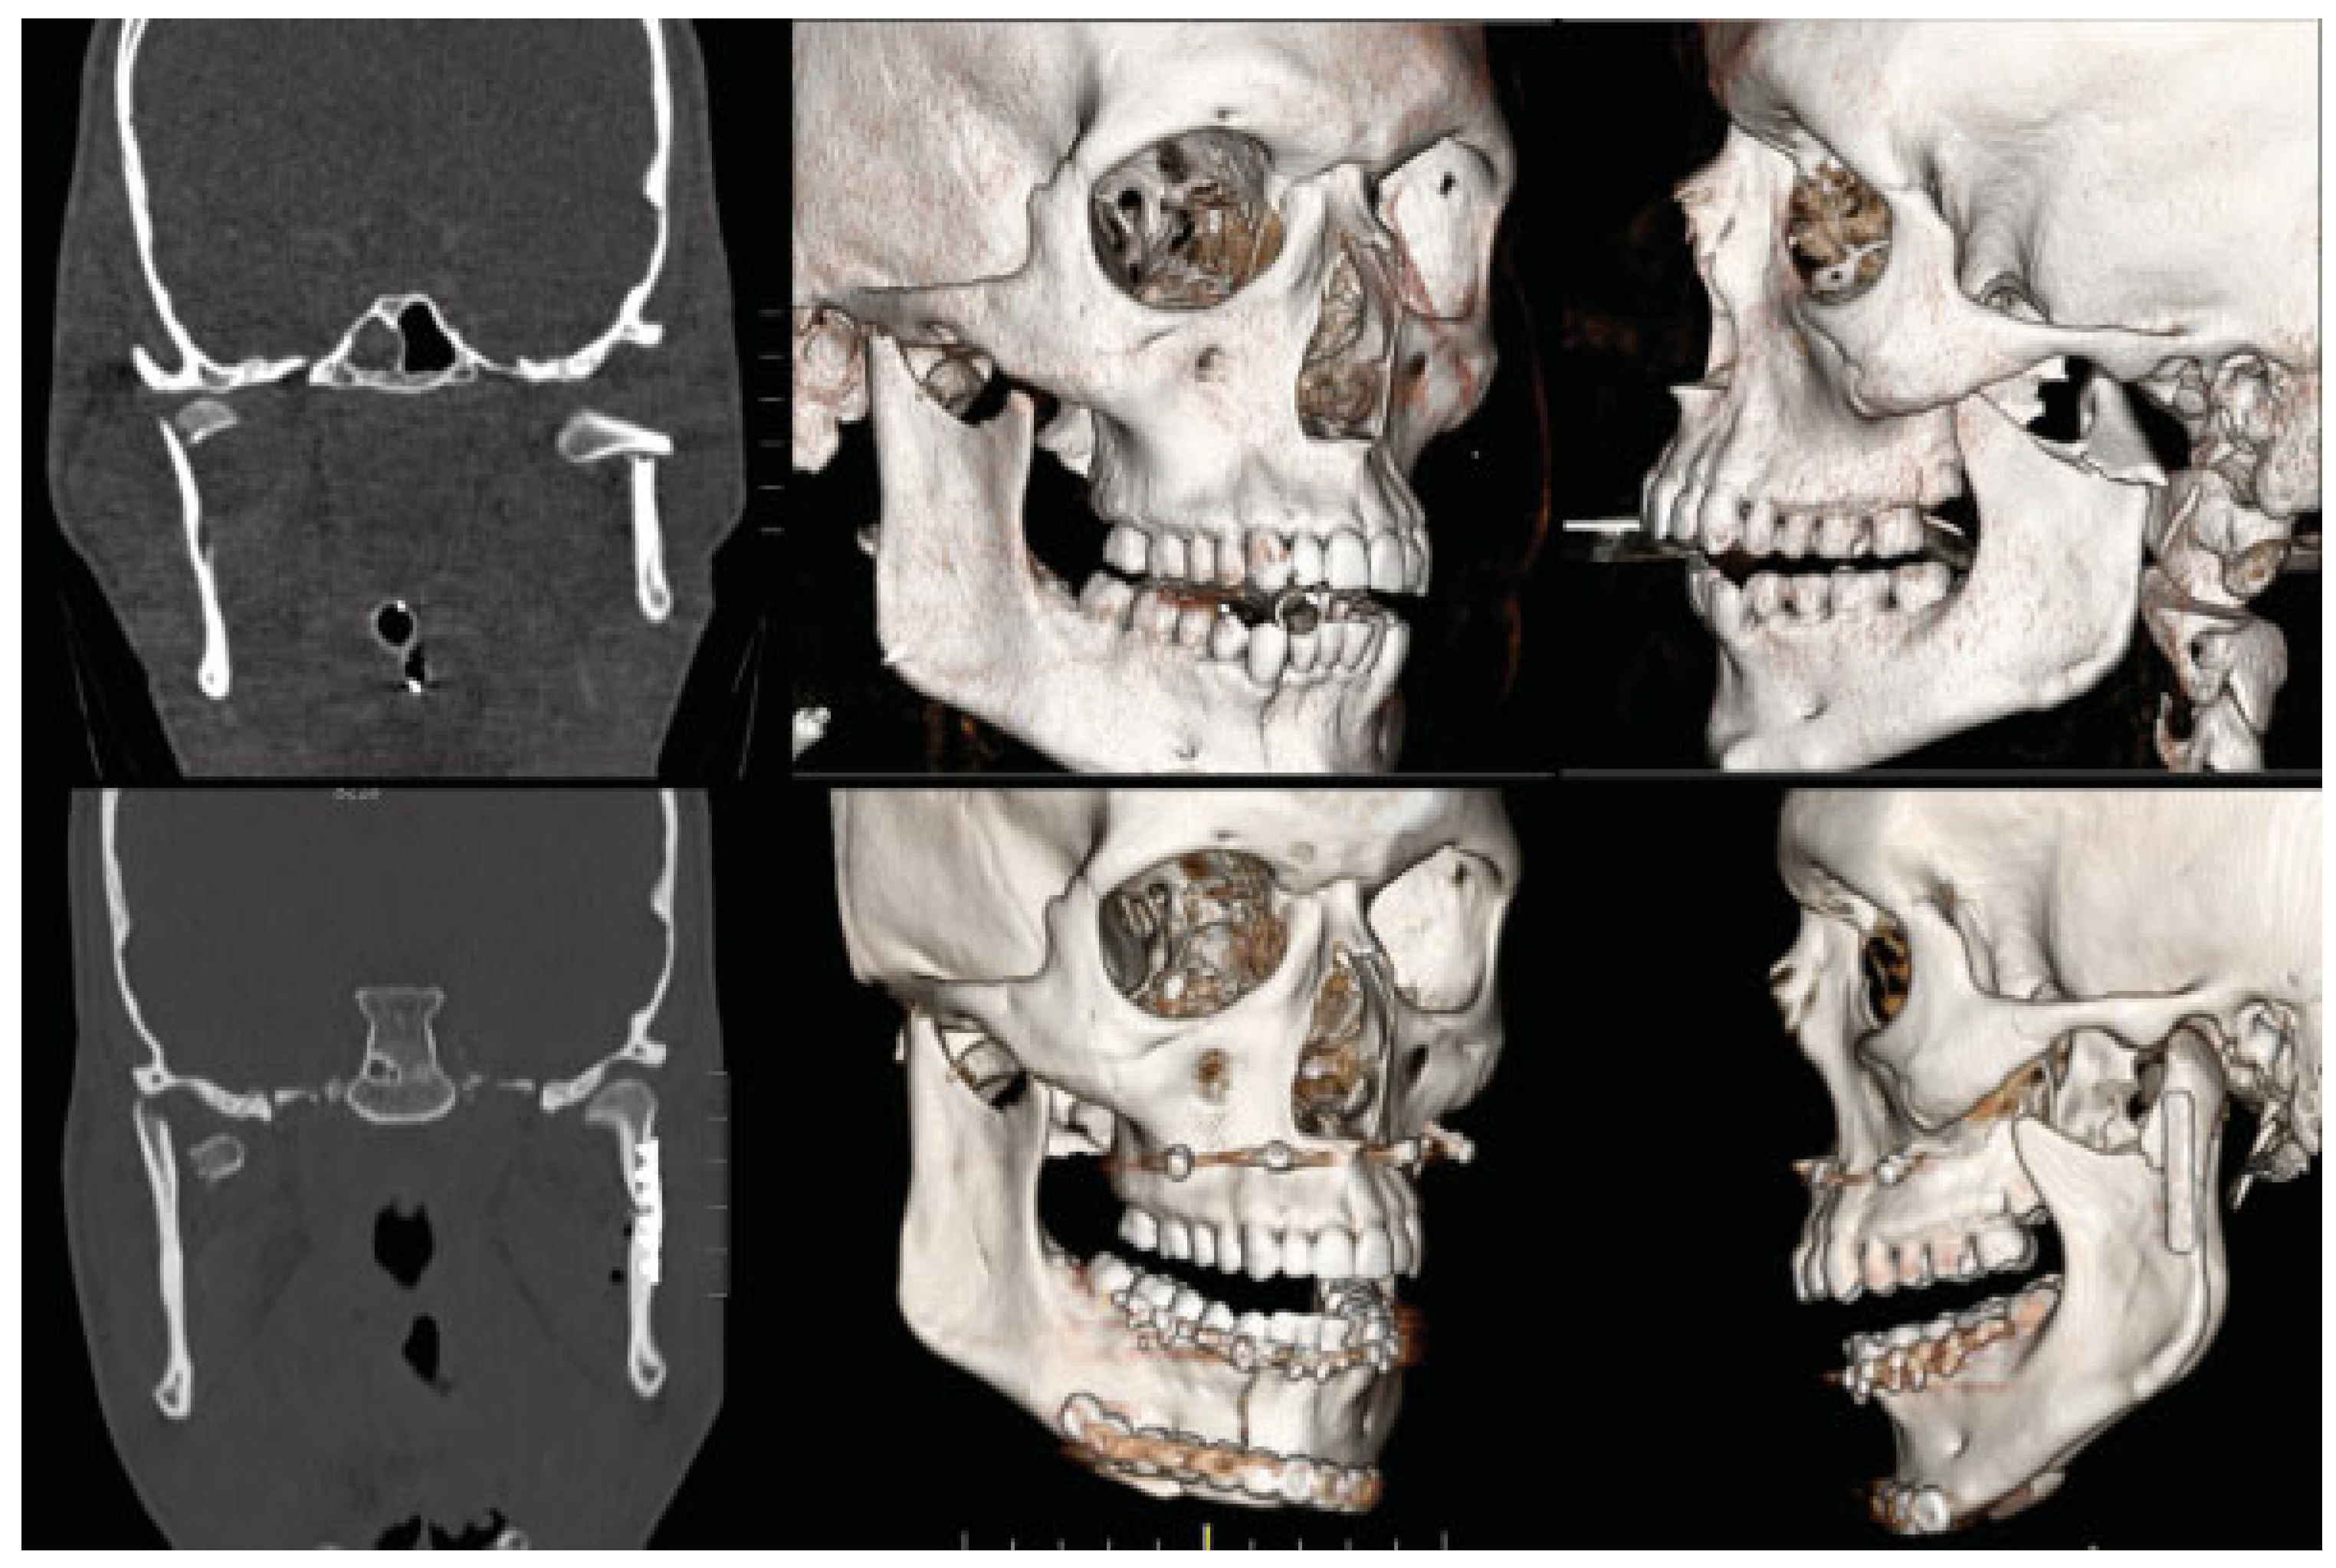

Case 1: Closed Treatment of Type I Injury

A 52-year-old man fell from a ladder and sustained bilateral condylar head fractures (type I) and a left parasymphyseal fracture (Figure 2). His anterior mandibular fracture was treated with rigid fixation with an inferior border plate and a tension band. Closed treatment of the condylar injuries was performed with arch bars and guiding elastic to allow for early range of motion. By 6 weeks after the injury, the patient had achieved a normal occlusion and a MMO of 40 mm. Long- term follow-up imaging at 2 years after injury demonstrated malunion of the condylar fractures without any appreciable functional consequences.

Figure 2. Type I bilateral condylar injury managed with closed treatment. Preoperative imaging demonstrating bilateral condylar head fractures with medial displacement (left). Postoperative CT after open reduction and internal fixation of the associated left parasymphyseal fracture and intermaxillary fixation showing that the fractured condylar fragments remained in a similar position as preoperatively (middle). CT imaging at 2 years after injury demonstrating that the condylar fractures have healed in a malunited position, but the patient has maintained a normal occlusion and adequate maximal mouth opening (right).